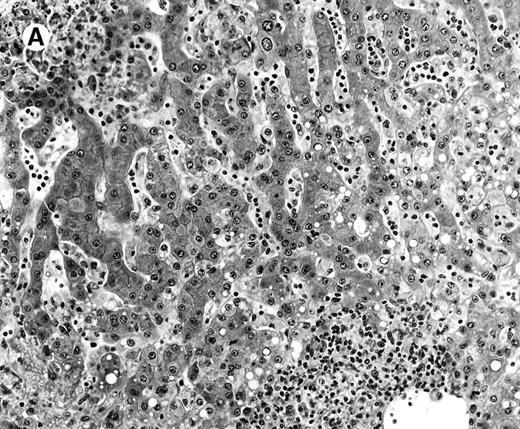

All cases showed essentially similar histologic findings in the liver and spleen. The splenic white pulp was inconspicuous to markedly depleted, whereas the sinusoids showed a prominent lymphoid infiltration (Figure 1A). There was striking hemophagocytosis within the splenic sinusoids (Figure 1B). The infiltrating lymphocytes were small and lacked significant cytologic atypia (Figure 1B). Immunoblasts and plasma cells were not prominent. The liver had prominent portal as well as sinusoidal infiltrates of small lymphocytes morphologically identical to those noted in the spleen (Figure 2). There was intracellular and intracanalicular cholestasis, steatosis, and focal necrosis. Hemophagocytosis was present within the sinusoids. In case 5, the spleen showed extensive areas of necrosis mainly in the perifollicular and periarteriolar lymphoid sheaths of the white pulp with the presence of immunoblasts reminiscent of IM.

Histologic findings in spleen.

(A) Section of spleen from case 2 shows depletion of white pulp and prominent sinusoidal small lymphoid infiltrates (hematoxylin and eosin, × 200). (B) The lymphocytes lack significant cytologic atypia. There is marked hemophagocytosis (hematoxylin and eosin, × 600).